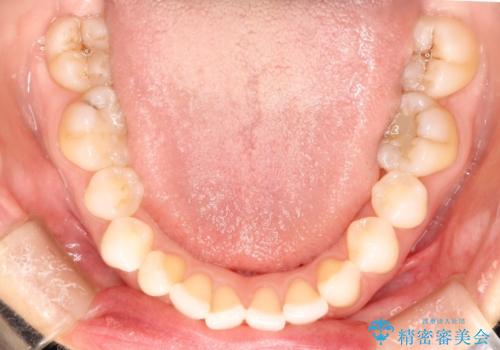

八重歯をマウスピース矯正で治療し、レーザーホワイトニングを行った症例

- 主訴:「右上犬歯を引っ込めて、歯並びをキレイにしたい」

右上の八重歯を気にされてご来院されました。結婚式を控えていたため挙式にまでに可能な限りキレイにしたいとのことでした。

右上の犬歯の歯茎は矯正前から退縮を起こしていましたが、矯正後もその退縮に関しては変化がありませんでした。今回は患者様が歯肉退縮に関しては治療をご希望ではありませんでしたが、当院ではこのように歯茎が下がり露出した根面を、歯茎を移植することでカバーし見た目を改善する手術を行っています。